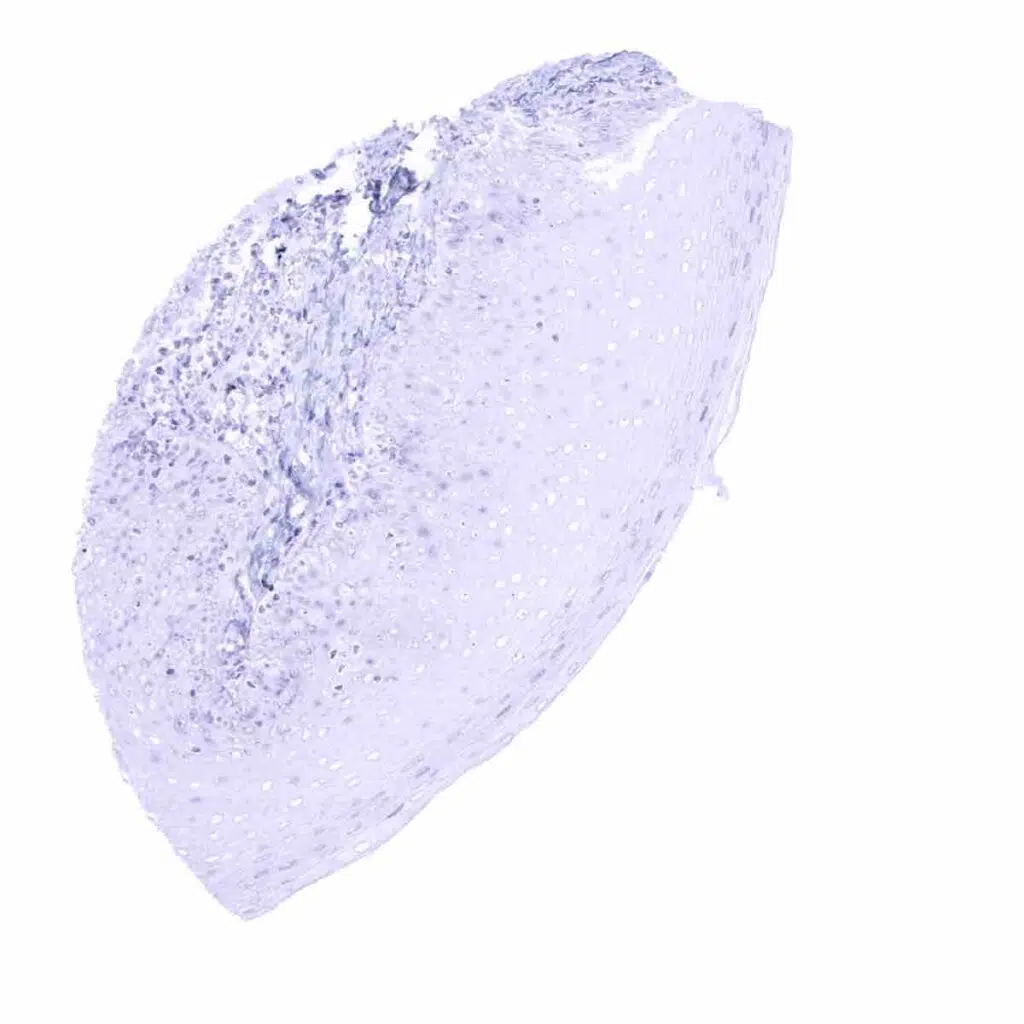

Spleen